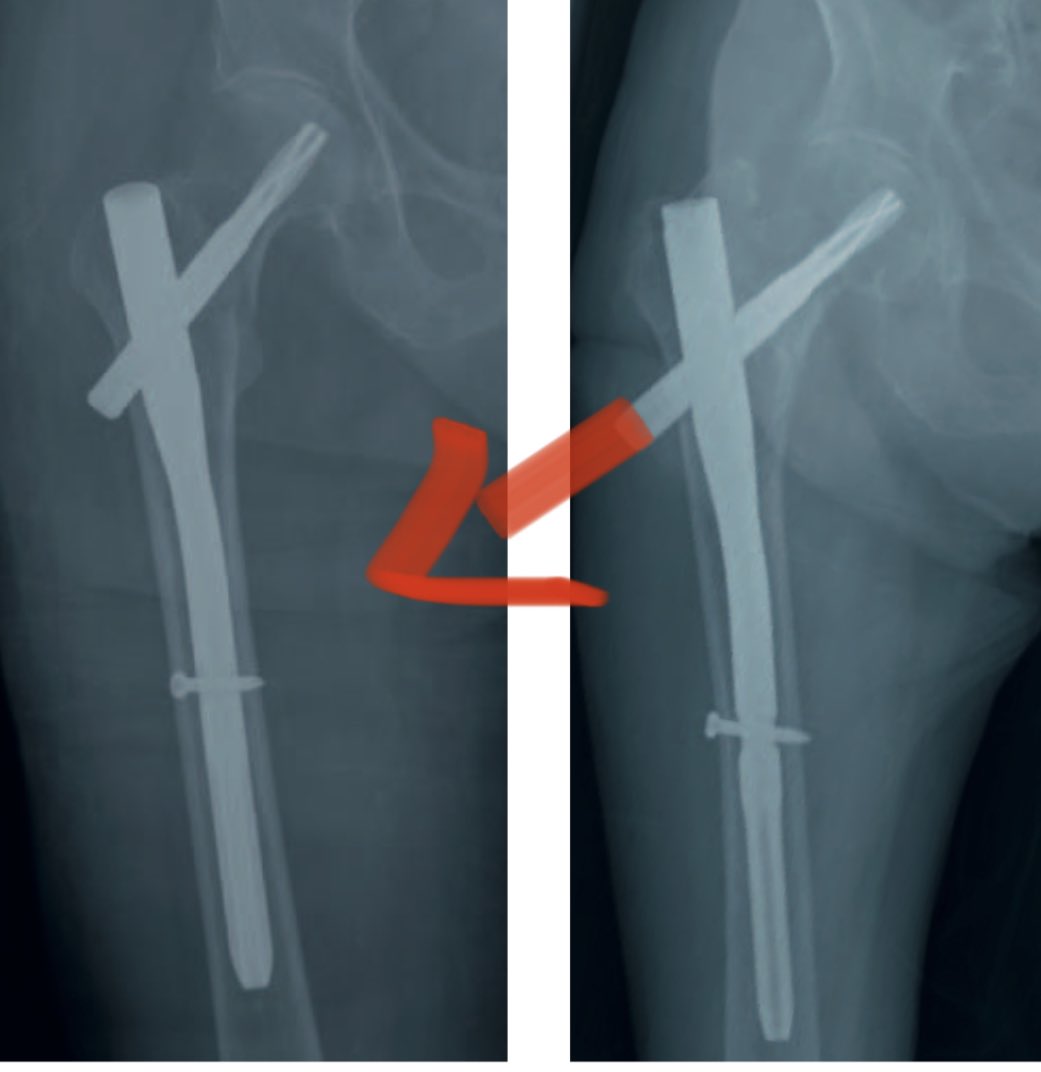

@orthohouse123 @traumacito @InvictaOrtho Challenge case! Its important to know what happens with the leg, physical examination, ct scan and pain. Open reduction with a nail, cables and some graft, its what i’d like to do

I'll take 'what is a stress-riser' for $500 thank, Phil